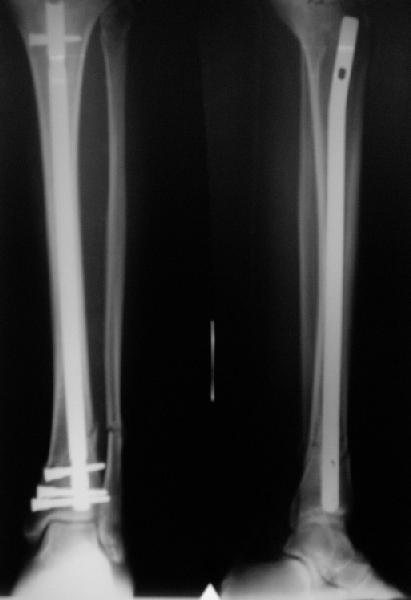

There are some more tricks which allow not to plate the fibula and provide good alignment and stability. A small wire distractor can provide alignment and restore length of both tibia and

fibula. Angular stability of the tibia is provided by insertion of more than two conventional medial-lateral locking screws. To maintain the position of the fibula perQ insertion of a single position screw often could be enough. I bet the articles didn't analyze the options.

A typical case is attached, also an image with intra-op reduction obtained by a small wire distractor, in the moment of insertion a Poller wire in AP direction. Fixation by a SIGN nail. Despite the fibula was not fixed healing was obtained with the unchanged alignment.

Very interesting application, but is the final position in a little distal varus with some fibula

distraction? Would that have been eliminated by fibula plating?

TDVC> Very interesting application, but is the final position in a

TDVC> little distal varus with some fibula distraction?

At least both the ankle mortise and tibial alignment look acceptable, don't they?

TDVC> Would that have been eliminated by fibula plating?

I am just trying to illustrate that prevention of 1)tibial valgus and 2)loss of reduction can be provided without fibular plating. Small changes of conventional nailing techniques allow to maintain reduction of the tibia reliably without adjunctive fibular stabilization.